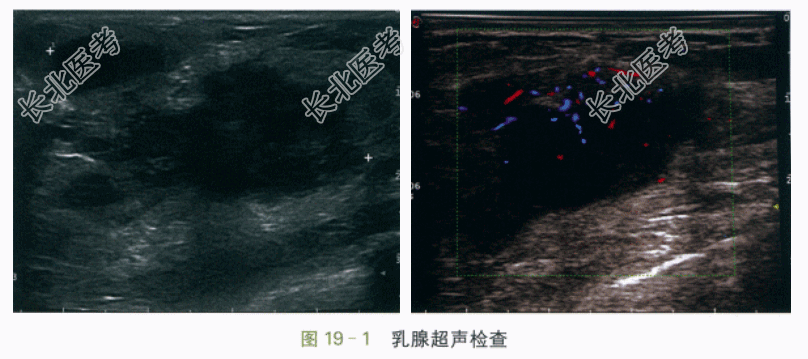

(2)乳腺B超检查结果(图19-1)提示:左侧乳腺可见一大小约49.3mm×27.9mm×43.1mm团块,位于3~4点钟方向,水平位生长,呈不规则形,边界清晰,边缘微小分叶,内部呈低回声,分布不均,部分向皮下延伸,内可见小片无回声区,后方回声无明显改变,CDFI示内边缘及中央区见较丰富血流信号,血管较细,走行规则。双侧腋窝及锁骨上未见明显异常肿大淋巴结。诊断意见:左侧乳腺实质性团块,拟BI-RADS-US4B类,考虑乳腺脓肿可能,请结合临床。